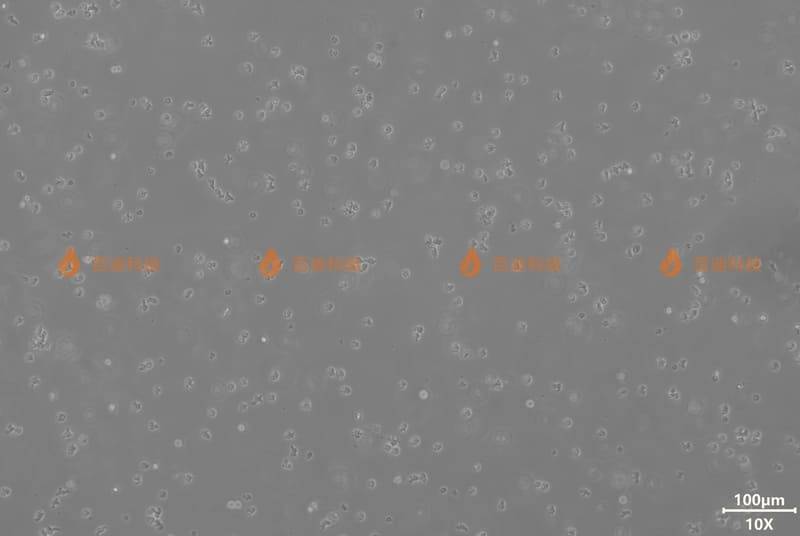

| 形態(tài) | 淋巴母細胞樣 |

| 產(chǎn)品簡介 | Reh細胞是從急性淋巴細胞性白血?。ˋLL)患者的組織中分離出的具有淋巴細胞形態(tài)的細胞,非B細胞也非T細胞類型,是一種前體B細胞。Reh細胞標志物表達情況:CD3A(17%)、CD3B(17%)、CD3C(20%),CD4(15%),CD10(55%)。Reh細胞可以用于3D細胞培養(yǎng)和免疫系統(tǒng)紊亂研究。 |